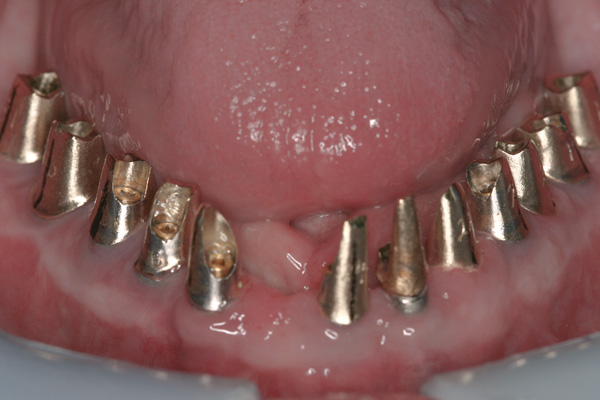

Background: This patient had a failing maxillary dentition and refused to wear a removable prosthesis. A staged approach was employed to retain some of his natural tooth abutments, and recession was noticed at the time of the impression for the second group of implants. Figure 1 shows the patient following insertion of the first set of implant custom abutments; the adjacent natural teeth are still present to support the provisional bridge. Seven months later, as shown in Figure 2, those first-stage custom abutments exhibited evidence of 1 mm to 3 mm of recession.

Results: A decision was made to re-prepare all of the abutments intraorally (Figure 3) so that all abutment margins would be at or below the gingival margin. (Of note, tooth Nos. 8 and 9, also shown in Figure 3, were later submerged for the case to be fully implant-supported.) While re-preparation greatly improved the esthetics of the final result, it required retraction cord placement, new impressions, and new castings.

Figure 2 After 7 months, the first-stage custom abutments exhibited evidence of 1 mm to 3 mm of recession.

Figure 2

Figure 3 Abutments re-prepared intraorally.

Figure 3